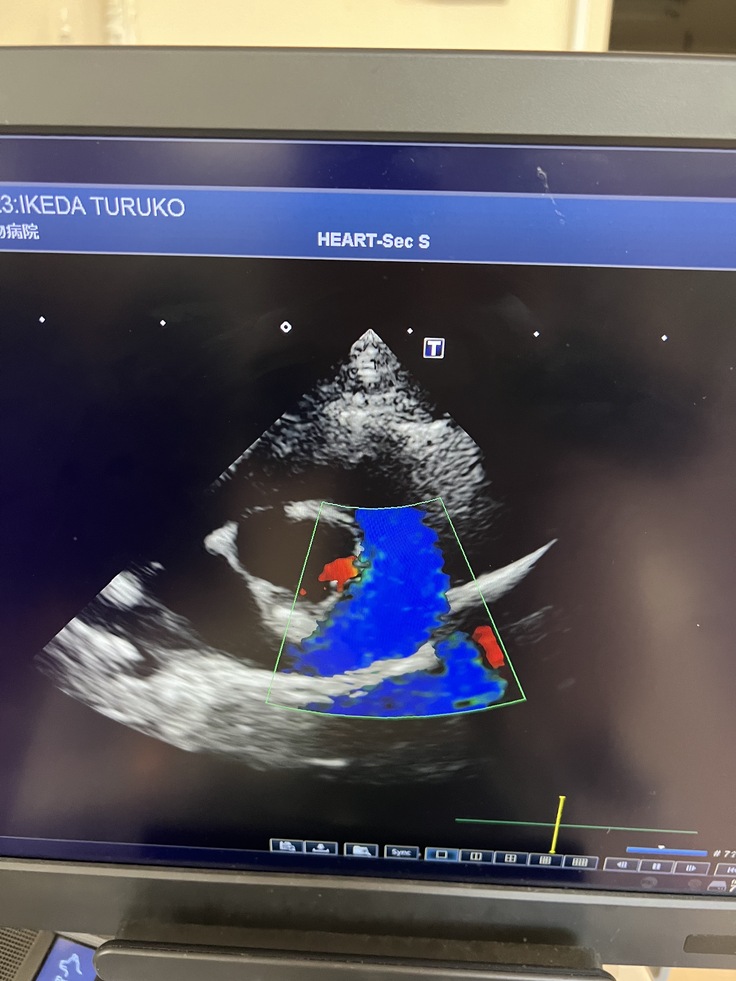

↑つる子のエコー